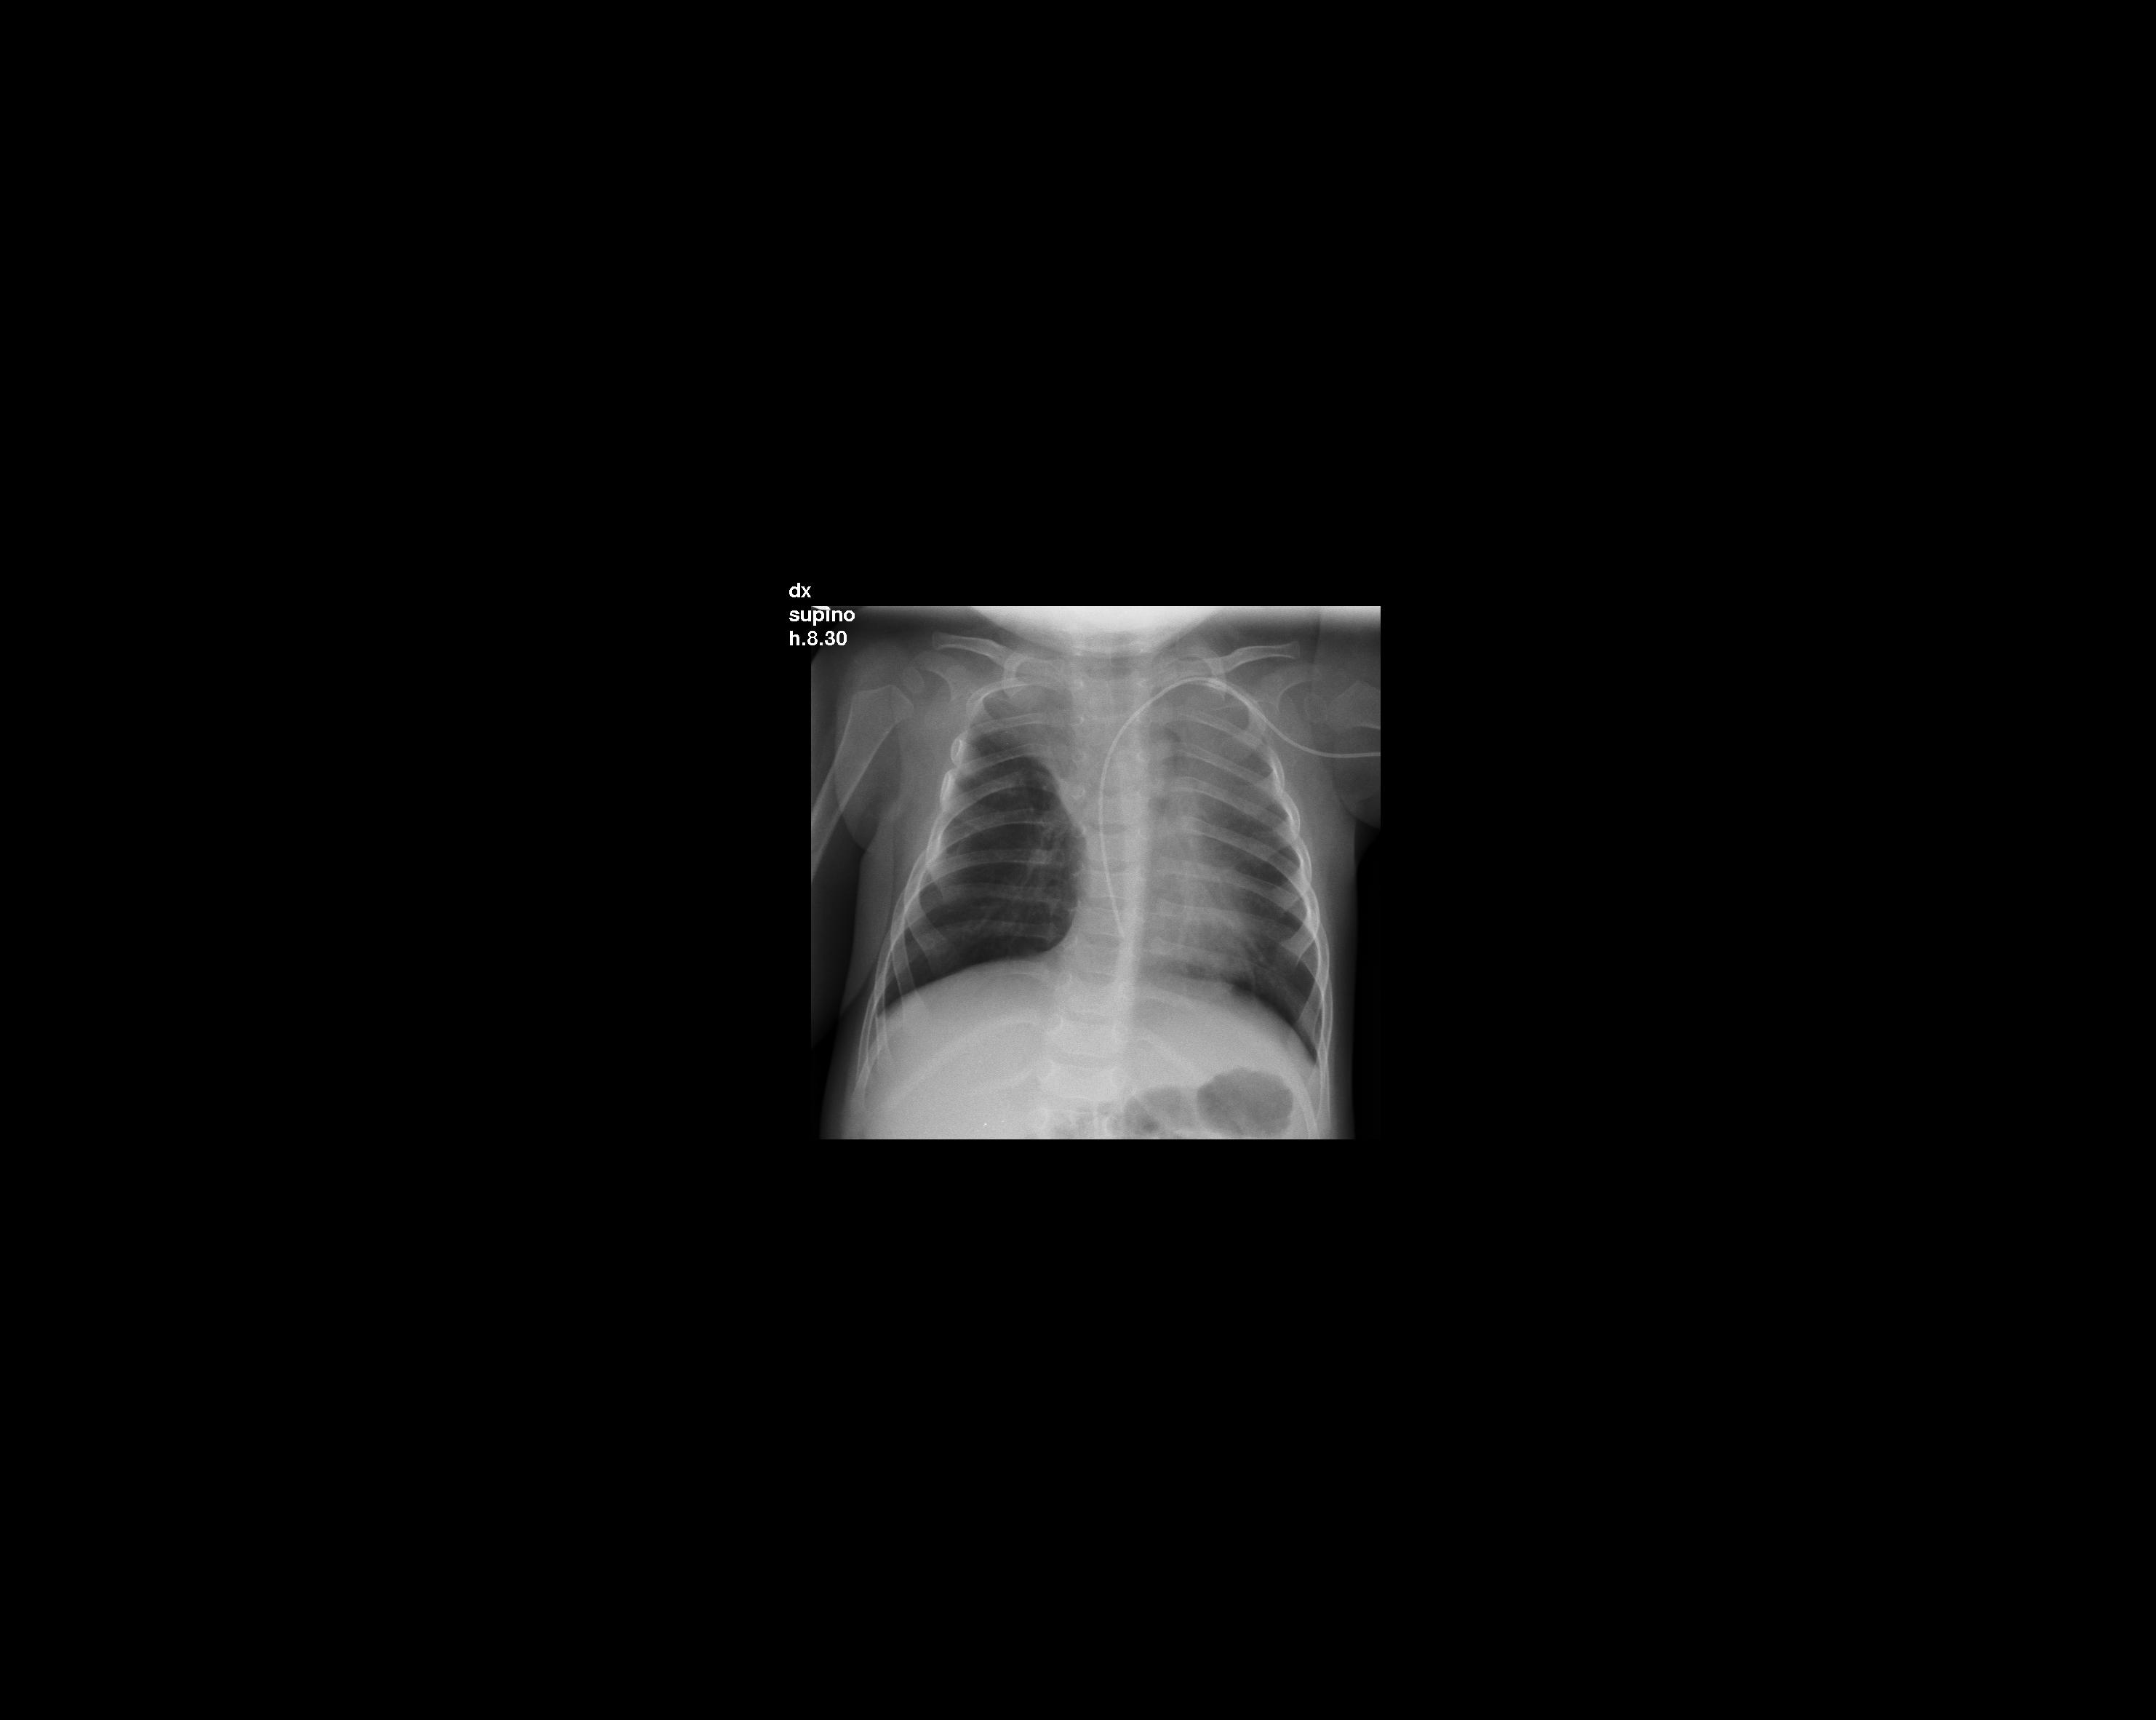

Nel corso della degenza in Rianimazione le condizioni generali del bambino vanno progressivamente migliorando. Sono comunque presenti rumori grossolani diffusi e persistenti su tutto l'ambito toracico. Dopo alcuni giorni la radiografia del torace, che fino a quel momento � progressivamente migliorata pur persistendo l'opacit� all'apice polmonare di destra (Figura 2), � assolutamente sconfortante, ed evidenzia una nuova opacit� al campo polmonare superiore di sinistra associata a broncogramma aereo in sede retrocardiaca sinistra con lieve deviazione mediastinica (Figura 3).

di destra con atelettasia del lobo superiore. Figura

2. Banda radiopaca atelettasica contro il III e IV spazio

intercostale di destra da riferire a residua atelettasia. Figura